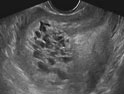

葡萄胎是指妊娠后胎盤絨毛滋養細胞增生,間質高度水腫,形成大小不一的水泡,水泡間相連成串,形如葡萄,亦稱水泡狀胎塊(HM)。葡萄胎分為兩類:①完全性葡萄胎 胎盤絨毛全部受累,整個宮腔充滿水泡,彌漫性滋養細胞增生,無胎兒及胚胎組織可見;②部分性葡萄胎 部分胎盤絨毛腫脹變性,局部滋養細胞增生,胚胎及胎兒組織可見,但胎兒多死亡,有時可見較孕齡小的活胎或畸胎,極少有足月嬰誕生。